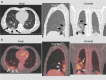

Methods: During the period of maximum incidence of the global pandemic in one of the most affected regions of Spain, there were 145 patients that met inclusion and exclusion criteria and were included in the study. Imaging findings previously described such as ground-glass opacities with low [18F]-FDG uptake were considered images suspicious for SARS-CoV-2 infection. Patients with these findings were referred to RT-PCR testing and close follow-up to confirm the presence or absence of COVID-19.

Results: Suspicious lung imaging findings were present in 7 of 145 patients (4.8%). Five of these 7 patients were confirmed as presenting SARS-CoV-2 infection, this is, COVID-19. In the remaining two, it was not possible to confirm the presence of COVID-19 with RT-PCR, although in one of them, PET/CT allowed an early diagnosis of a lung infection related to a bacterial pneumonic infection that was promptly and adequately treated with antibiotics.